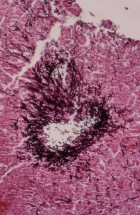

Делатност Одељења обухвата истраживачки и специјалистичко – стручни рад. Одељење се бави клиничком, патоанатомском, патохистолошком, имунохистохемијском и молекуларном дијагностиком обољења домаћих и дивљих животиња, као и патологијом репродукције. Рад на одељењу је организован кроз теренске и лабораторијске активности.

- Патохистолошка, цитолошка, имунохистохемијска и молекуларна дијагностика;